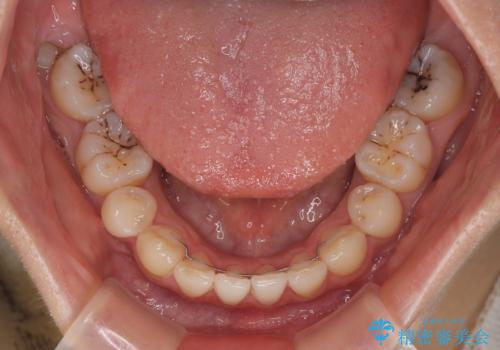

欠損や残存乳歯、深い咬み合わせ ワイヤー矯正で咬合改善

甚大な咬合力に抵抗して過蓋咬合を改善する必要があり、更には口元が引っ込みすぎることがないように仕上げていく必要もあったため、治療期間は3年を超えましたが、当初計画通りの仕上がりで治療を終えることができました。